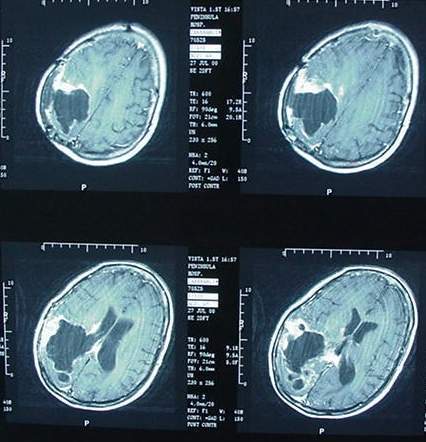

Il y a également un lien évident aujourd'hui entre la multiplication des réseaux mobiles, l'utilisation massive et intensive des technologies mobiles et la recrudescence de cancer cérébral.

Ainsi, de nombreuses études depuis 10 ans traitent de ce lien entre champs électromagnétiques de la téléphonie mobile et tumeur cérébrale. Les voici :

Les données statistiques révèlent une recrudescence des cancer du cerveau depuis plus de 10 ans.

Il s'agit d'une augmentation de 50% des tumeurs du cerveau chez les enfants au Royaume-Uni en 10 ans, de plus de 40% au Danemark et en Finlande et d'une explosion du phénomène en France.

Les chiffres ont été publiés par le Bureau des statistiques nationales au Royaume-Uni en 2012. Il indiquent une augmentation de 50 pour cent des tumeurs des lobes frontaux et temporaux chez les enfants entre 1999 et 2009.

Le 31 mai 2011, le Centre international de recherche sur le cancer (Circ) à Lyon, organisme de l'Organisation mondiale de la santé, classait comme "peut-être cancérogène pour l'homme" (2B) les champs électromagnétiques de radiofréquences, autrement dit les ondes émises par les téléphones mobiles, les experts se sont basés sur une étude montrant un risque de gliome accru de 40% chez des "gros" utilisateurs de téléphone portable (30 minutes/ jour en moyenne sur 10 ans).